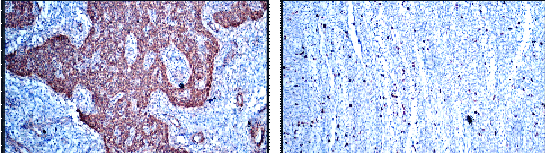

Expanded nerve fascicles with a low-grade neoplasm composed of uniform plump spindle to oval with increased vascularity; features are not of a nerve sheath tumor. Histopathology was inconclusive so Immunohistochemistry was advised.

Immunohistochemistry

Smooth muscle actin – positive, calponin – positive, and S-100, epithelial membrane antigen and CD 34 negative, confirmed the diagnosis of glomus tumor of the sciatic nerve [6,2] (Fig. 6).

Figure 6: Immunohistochemistry showing positive for Calponin and K67 markers.